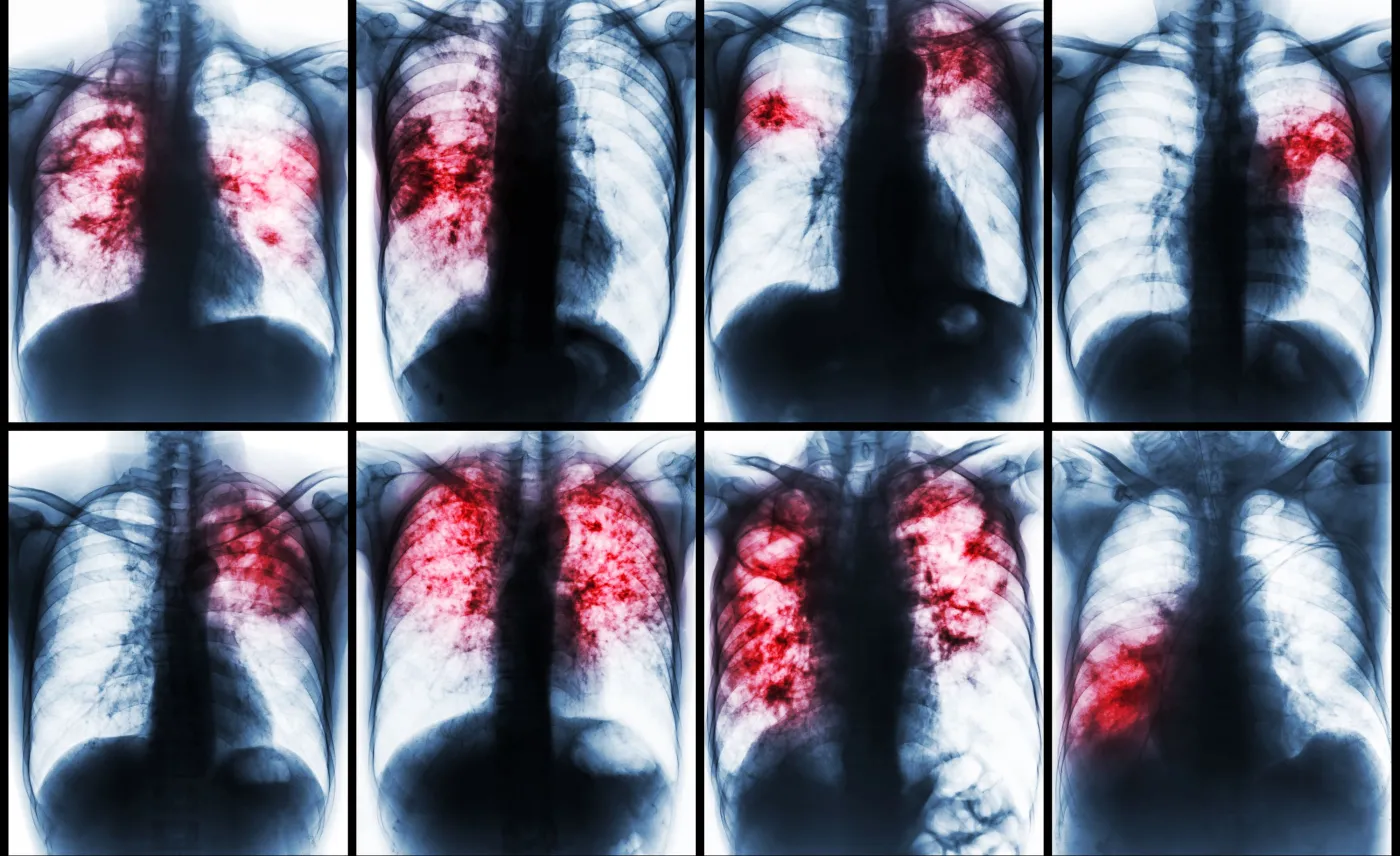

Jak zauważają specjaliści, gruźlica to jeden z pięciu największych zabójców ludzkości. Dominuje w krajach rozwijających się, jednak jest obecna też w Polsce. – W niektórych państwach można mówić o epidemii. Często są to szczepy oporne na leki przeciwgruźlicze – zaznacza Paweł Grzesiowski.